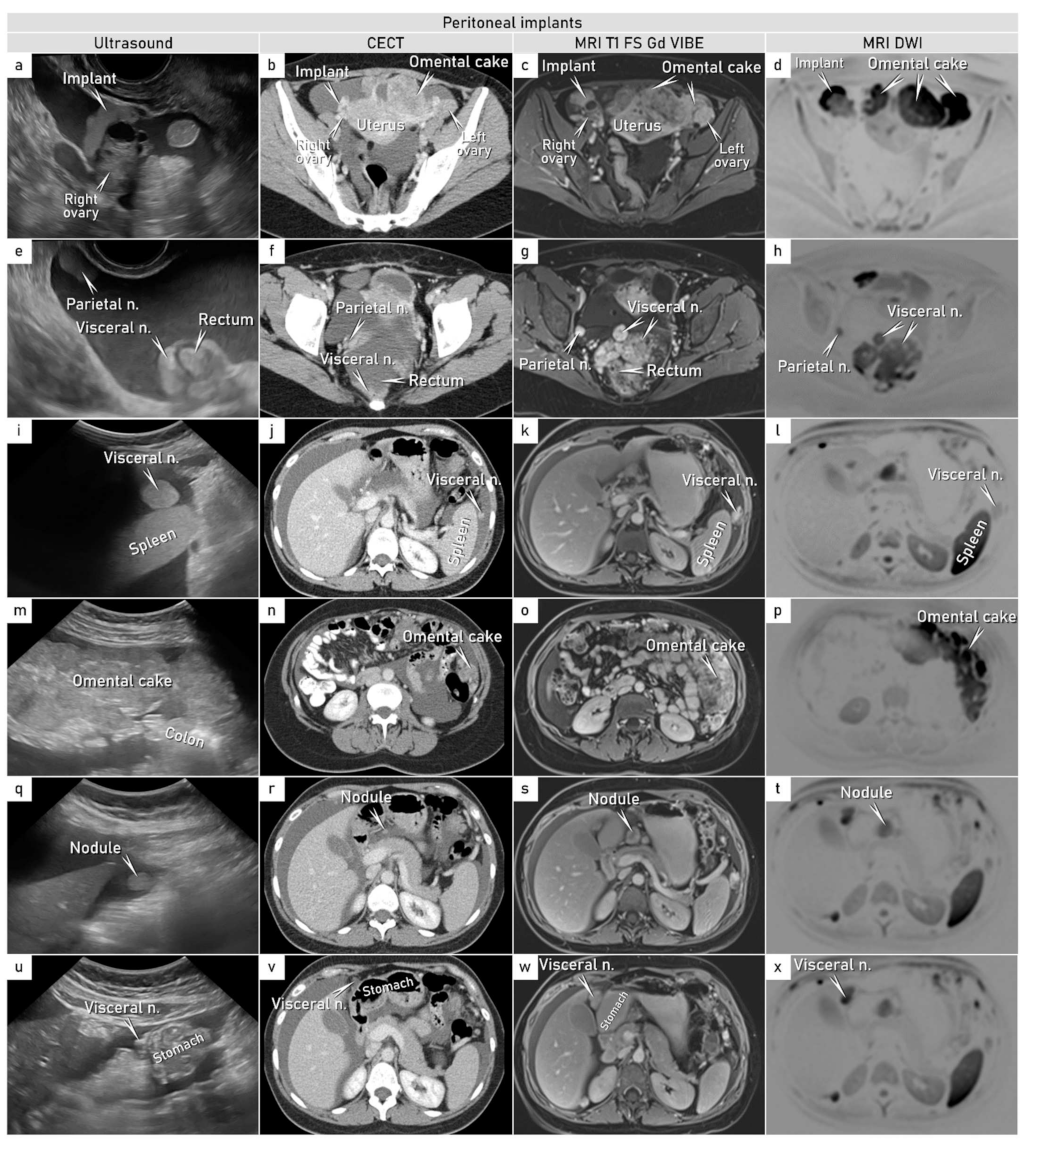

- Hanbidge, A.E.; Lynch, D.; Wilson, S.R. US of the peritoneum. Radiographics 2003, 23, 663–684, discussion 684–665. [Google Scholar] [CrossRef] [PubMed]